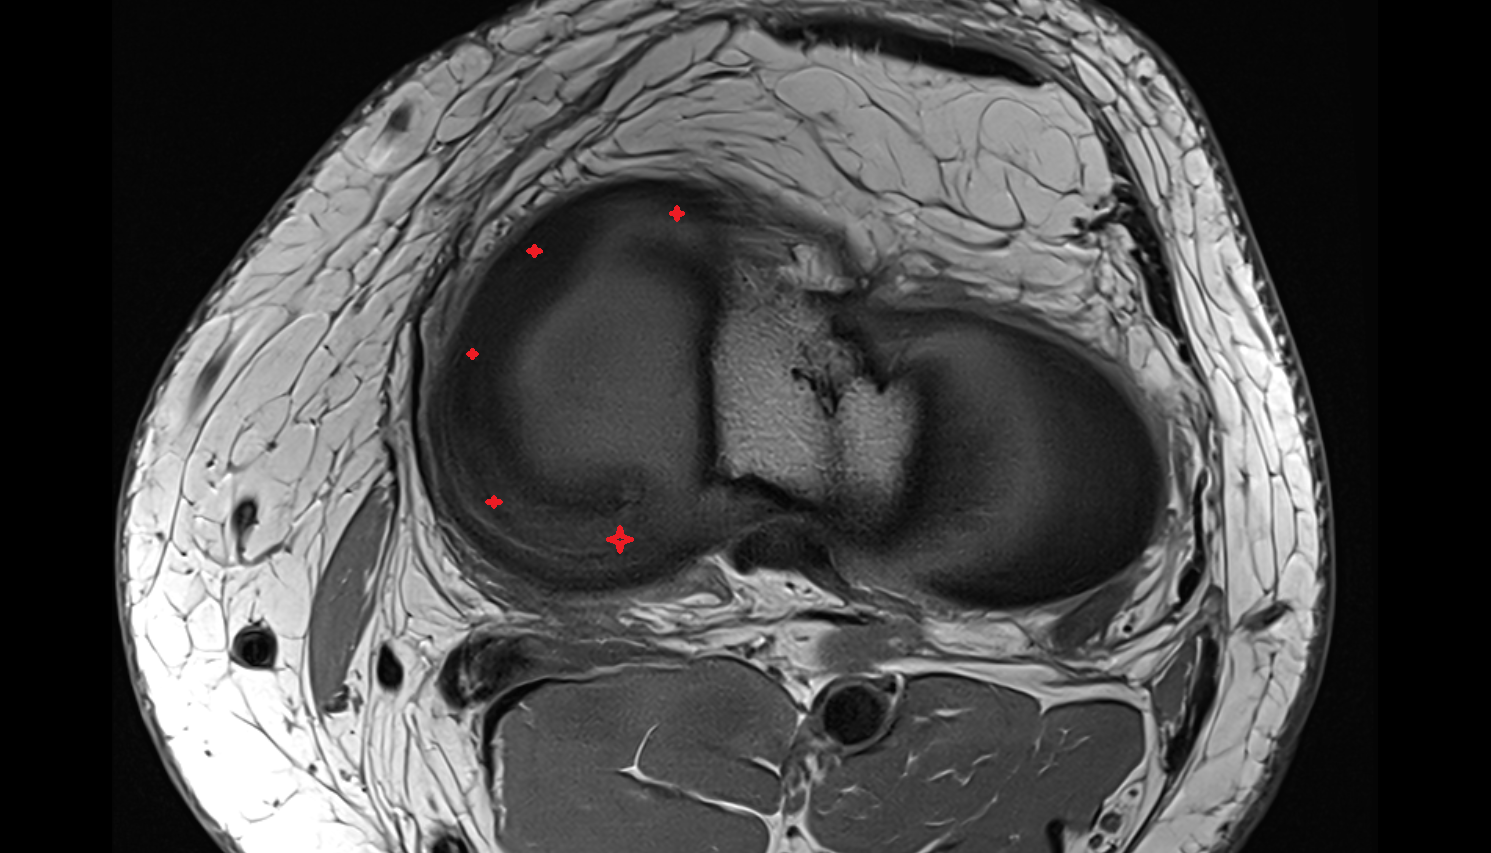

- Meniscus cartilage

- Medial meniscus

- Lateral meniscus

- Anterior horn of medial meniscus

- Posterior horn of medial meniscus

- Body of medial meniscus

- Anterior root of medial meniscus

- Posterior root of medial meniscus

- Anterior horn of lateral meniscus

- Posterior horn of lateral meniscus

- Body of lateral meniscus

- Anterior root of lateral meniscus

- Posterior root of lateral meniscus